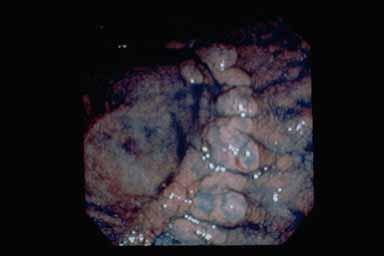

Early gastric malignant lymphoma with pyloric stenosis

Tokyo Pref., Cooperative study between National Cancer Center and Kyushu Cancer Center

Malignant Lymphoma/Malignant lymphoma

Stomach/More than one of above

Endoscopy

40 -

submucosa